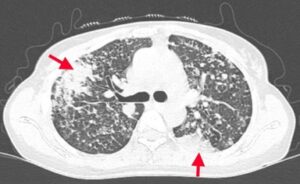

CASE LÂM SÀNG: ĐIỀU TRỊ UNG THƯ PHỔI TẾ BÀO NHỎ BẰNG THUỐC MIỄN DỊCH KẾT HỢP VỚI HOÁ TRỊ TẠI BỆNH VIỆN BẠCH MAI

CASE LÂM SÀNG: ĐIỀU TRỊ UNG THƯ PHỔI TẾ BÀO NHỎ BẰNG THUỐC MIỄN DỊCH KẾT HỢP VỚI HOÁ TRỊ TẠI BỆNH VIỆN BẠCH MAI GS. TS. Mai Trọng Khoa, PGS. TS. Phạm Cẩm Phương, PGS. TS. Phạm Văn Thái, BSCKI. Nguyễn Thu Trang, BSNT. Đỗ Thị Thanh Xuân Trung...